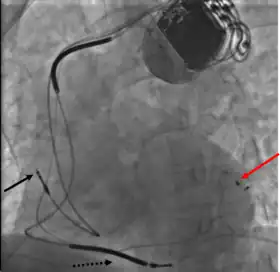

CRT devices have at least two leads, one passing through the vena cava and the right atrium into the right ventricle to stimulate the septum, and another passing through the vena cava and the right atrium and inserted through the coronary sinus to pace the epicardial wall of the left ventricle. Often, for patients in normal sinus rhythm, there is also a lead in the right atrium to facilitate synchrony with the atrial contraction. Thus, the timing between the atrial and ventricular contractions, as well as between the septal and lateral walls of the left ventricle can be adjusted to achieve optimal cardiac function.

A pacemaker may be implanted whilst a person is awake using local anesthetic to numb the skin with or without sedation, or asleep using a general anesthetic.[25] An antibiotic is usually given to reduce the risk of infection.[25] Pacemakers are generally implanted in the front of the chest in the region of the left or right shoulder. The skin is prepared by clipping or shaving any hair over the implant site before cleaning the skin with a disinfectant such as chlorhexidine. An incision is made below the collar bone and a space or pocket is created under the skin to house the pacemaker generator. This pocket is usually created just above the pectoralis major muscle (prepectoral), but in some cases the device may be inserted beneath the muscle (submuscular).[26] The lead or leads are fed into the heart through a large vein guided by X-ray imaging (fluoroscopy). The tips of the leads may be positioned within the right ventricle, the right atrium, or the coronary sinus, depending on the type of pacemaker required.[25] Surgery is typically completed within 30 to 90 minutes. Following implantation, the surgical wound should be kept clean and dry until it has healed. Some movements of the shoulder within a few weeks of insertion carry a risk of dislodging the pacemaker leads.[25]